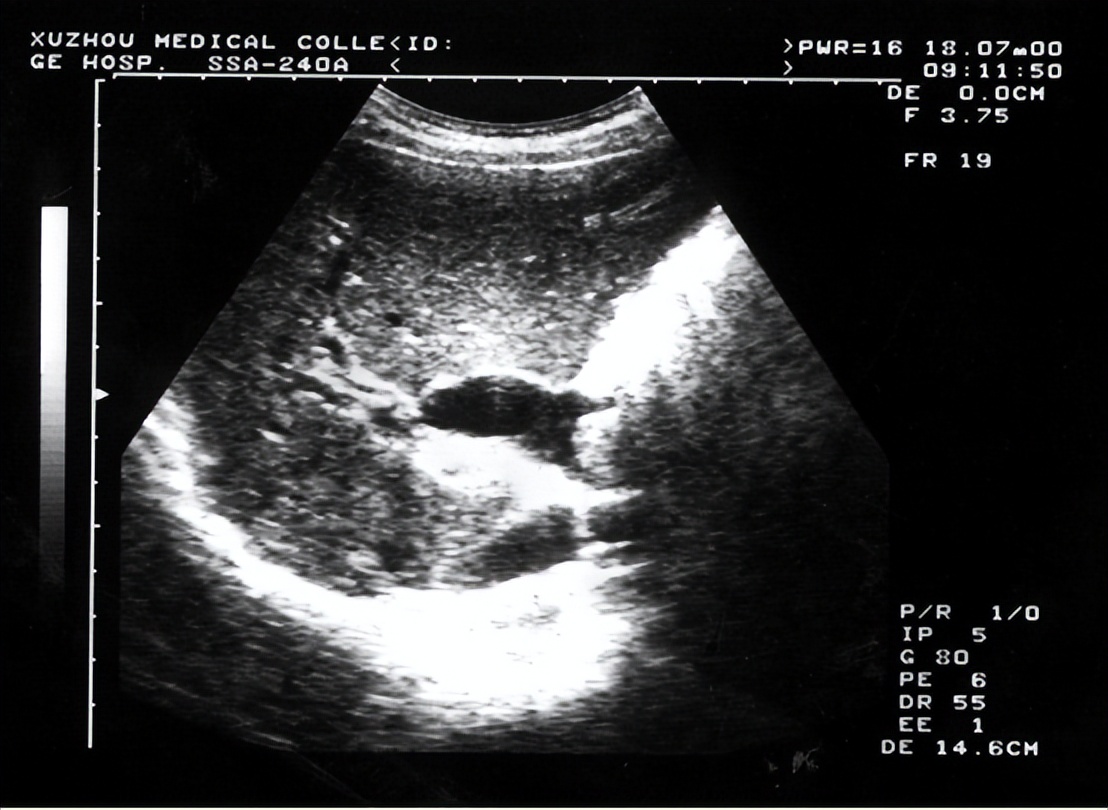

2.腹部超声

随着超声仪器的不断优化以及超声科技师技术的提高,超声对腹腔游离气体的敏感性得到显著提高,其在消化道穿孔中的应用也日益受到关注。

相对于腹部X线片,超声对于少量游离气体更为敏感,并且可以通过改变体位及加压法使其检测率得到进一步提高。